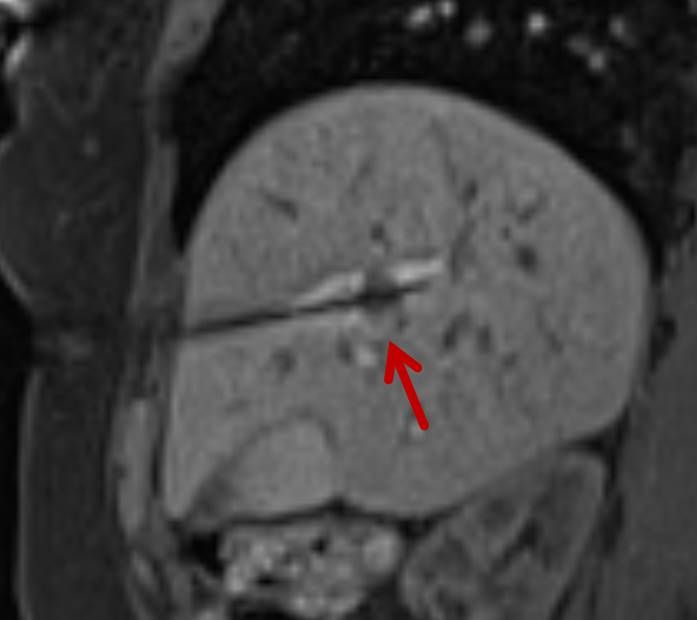

Eine Voraussetzung für die vollständige chirurgische Entfernung von Knochen- und Weichteiltumoren ist die präzise Erkennung der Tumorausdehnung und der Tumorgrenzen. Mit der Kernspintomographie (MRT) kann das Tumorgewebe exzellent von gesundem Gewebe abgegrenzt werden und somit die Ausdehnung vor der Operation bestimmt werden. Nach der kernspintomographischen Bestimmung der Tumorausdehnung werden unter kontinuierlicher MRT-Bildgebung die Grenzen des Tumors markiert. Die Marker werden mit einer Nadel ins angrenzende gesunde Gewebe eingebracht. Die Markierung kann am Tage vor der Operation durchgeführt werden. Alternativ ist die Tumormarkierung auch mit anderen bildgebenden Verfahren möglich, z.B. mit der Computertomographie oder dem Ultraschall.

Abbildung: Bei diesem Patienten wurde ein im Röntgen nur schlecht sichtbarer Knochentumor vor der Operation unter MRT-Kontrolle mit kleinen röntgendichten Spiralen („Coils“) markiert. Damit hat der Operateur eine optimale Darstellung des Tumorbereichs bzw. der Tumorgrenzen und kann gezielter, schonender und effektiver operieren.